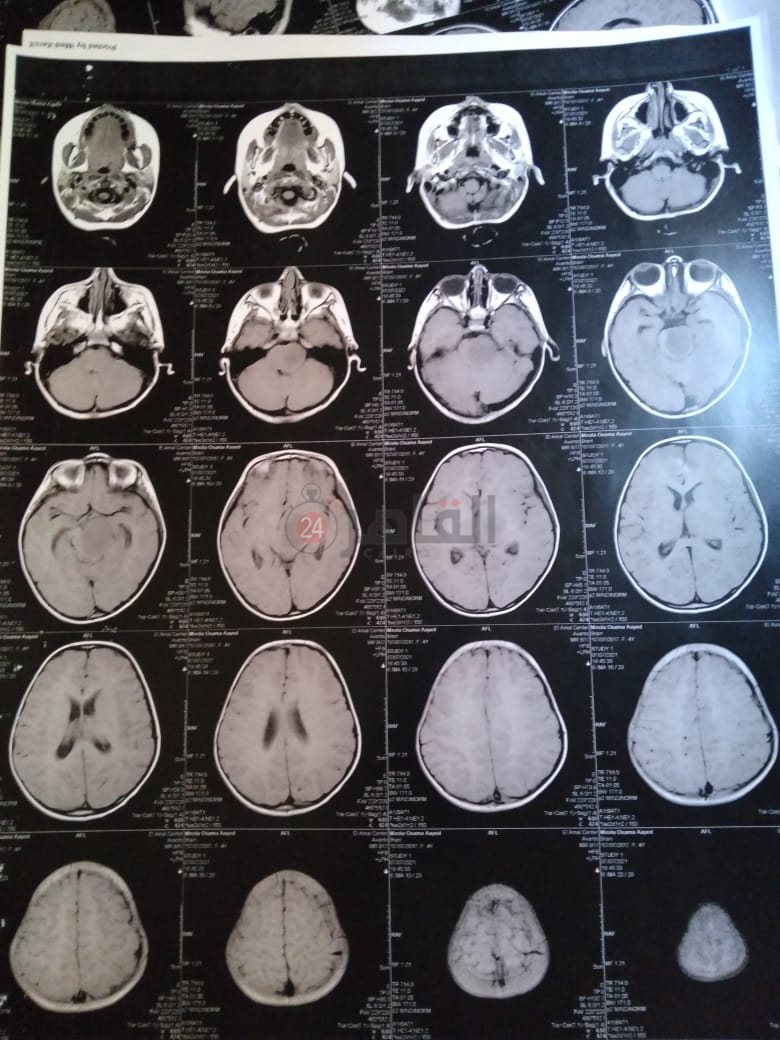

وأضاف: "أجرينا أشعة مقطعية لها لم يظهر بها أي شيء، ثم طلب الطبيب إجراء أشعة رنين على المخ، وهنا تبين وجود بؤرة سرطانية بالمخ، مشيرًا إلى أن:" الدكتور طلب مني أذهب إليه لوحدي من غير الأم والبنت، وقالي إن في ورم بس مش عارفين نوعه خبيث ولا حميد".

وأوضح أن حالة نجلته تتدهور بسرعة كبيرة، حيث أصُيبت حاليًا بشلل نصفي بالجانب الأيمن، لأن البؤرة حجمها 2.5 سم في 4.5 سم، ومرتكزة على جانبها الأيمن، مشددًا على أنها الحالة الأولى في العائلة التي تصاب بهذا المرض.